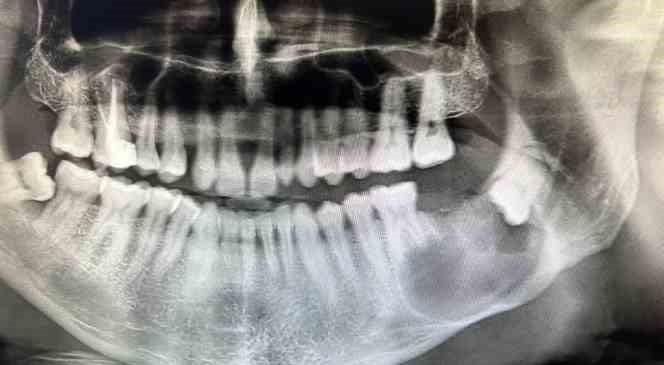

37 numaralı dişi çekilen hastanın tomografi görüntüleri çekildi. Hastanın 3D yazıcı sistemi ile çene modeli oluşturuldu. Oluşturulan 3D çene modeli üzerinde metal plak denemesi yapıldı. Denemenin ardından Ağız, Diş ve Çene Cerrahisi Uzmanı Yunus Balel, genel anestezi altında hastayı ameliyat ederek metal plak işlemini hastaya uyguladı.